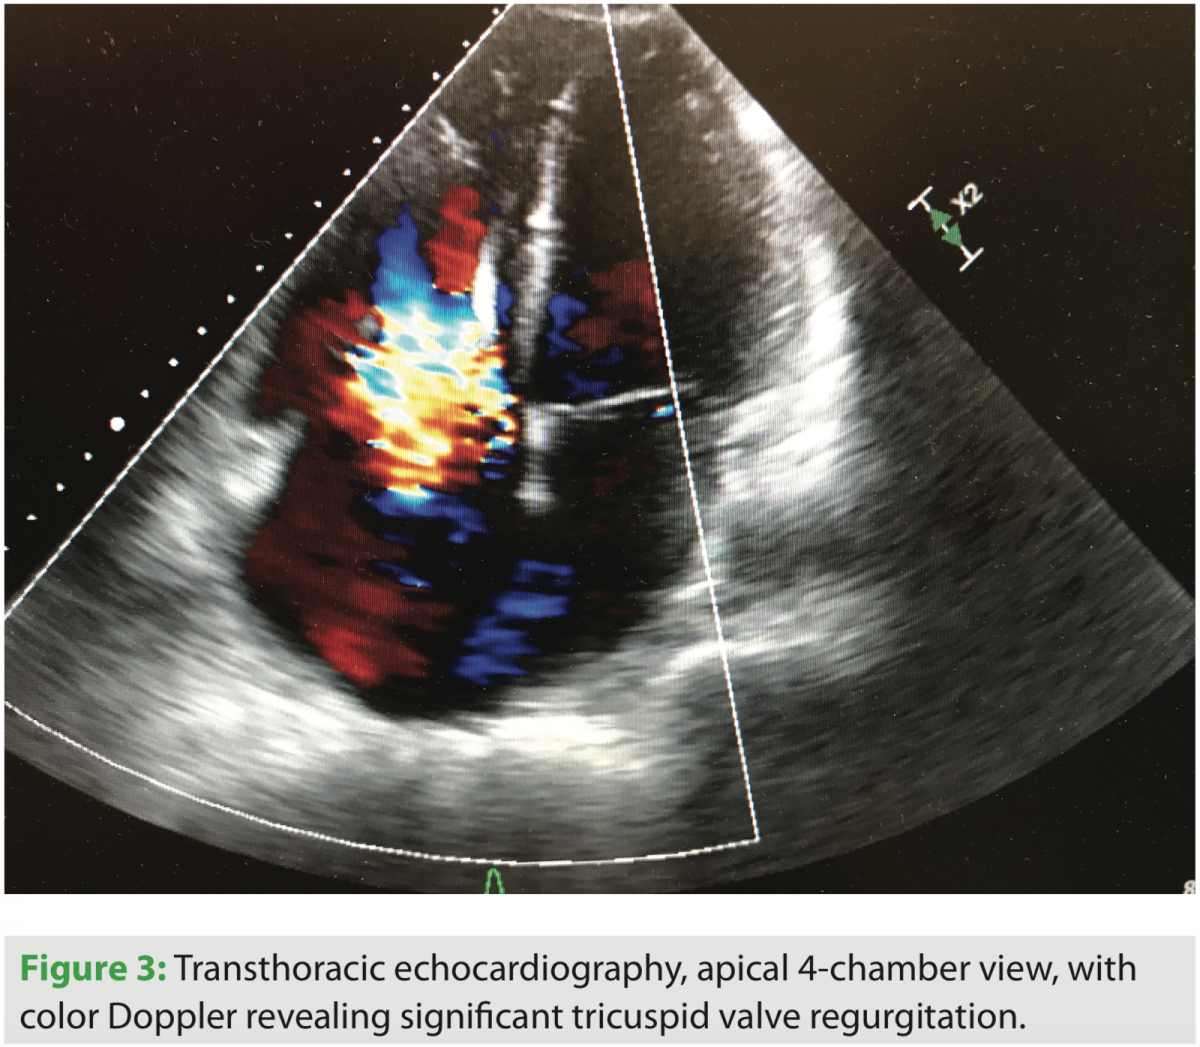

After admission and diuresis, significant symptomatic improvement occurred, and the patient was nearing his perceived dry weight based on initial clinic visits and recorded weights from home. Standard two- and three-dimensional transthoracic echocardiography were performed, and significant tricuspid valve regurgitation was seen. The course of the right ventricular lead can be seen in several views, along with its interaction with the TV leaflet and interventricular septum (Figures 1, 2, and 4). Corresponding tricuspid valve dysfunction is appreciated with severe tricuspid valve regurgitation on Doppler echo images (Figures 3 and 5). The RV was felt to be moderately dilated with a mid-RV diameter of 3.5 cm. Significant RV systolic dysfunction was seen and felt to be moderate with a tricuspid annular plane systolic excursion (TAPSE) of 1.25 cm. The tricuspid valve regurgitation was severe with a vena contracta width of 0.9 cm and PISA radius of 1.0 cm. LV systolic function was essentially unchanged, with an EF of 25%. The bioprosthetic aortic valve was well seen and without significant dysfunction.